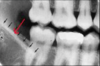

identify the anatomical structure below.

incisive (nasopalatine) foramen